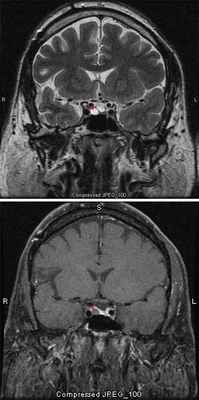

Диагностика аденомы гипофиза: тщательные гормональное и офтальмологическое обследования и нейровизуализация. Магнитно-резонансная томография — основной метод диагностики, позволяет выявить аденомы размерами менее 5 мм, однако, даже с учётом этого, примерно у 25–45% пациентов визуализировать аденому не удаётся. Компьютерную томографию применяют только в экстренных ситуациях при невозможности провести магнитно-резонансной томографии для исключения тяжёлых осложнений.

МРТ со срезами толщиной 1 мм

Вопрос об исключении опухоли гипофиза ставят при наличии головных болей, характерных расстройств зрения и эндокринопатии. Проводят нейровизуализационные исследования с толщиной среза 1 мм. МРТ более чувствительна, чем КТ, особенно для выявления микроаденом.